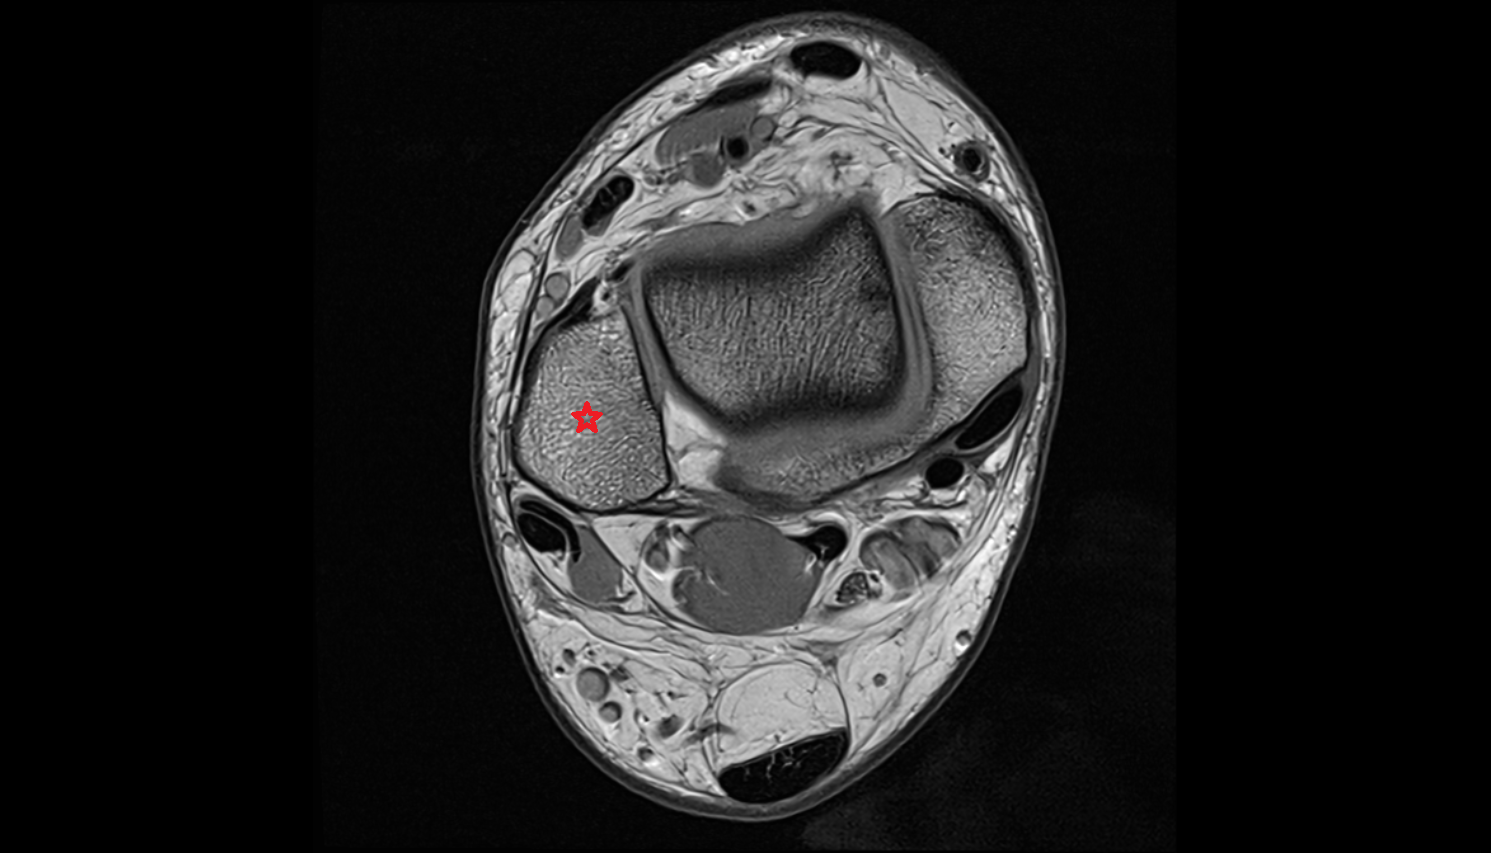

- Talus

- Body of talus

- Calcaneus

- Sustentaculum tali

- Medial malleolus

- Lateral malleolus

- Ankle joint

- Talocalcaneal joint

- Tibialis posterior muscle

- Flexor digitorum longus muscle

- Flexor hallucis longus muscle

- Tibialis posterior tendon

- Flexor digitorum longus tendon

- Flexor hallucis longus tendon

- Achilles tendon